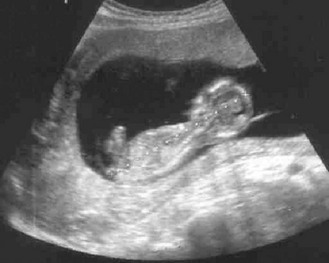

Normal findings: Abdominal organs are displaced during pregnancy so swelling may be difficult to identify, e.g. ovarian cyst, and pain and tenderness may not be in usual sites. The kidneys and liver cannot be palpated and listening for bowel sounds may be difficult in late pregnancy. In tall or thin patients, the SFH may be less than expected; in obese patients, it may be larger. Ultrasound scanning is now routinely used to assess fetal development (Figs 10.42 and 10.43).

Abnormal findings: After 25 weeks’ gestation a difference of 3 or more between the number of completed weeks of pregnancy and the SFH in centimetres may suggest that the baby is small or large for dates. Investigate this with ultrasound. From 36 weeks a lie other than longitudinal is abnormal and requires further investigation or treatment. Do not routinely listen to the fetal heart unless the mother requests this.